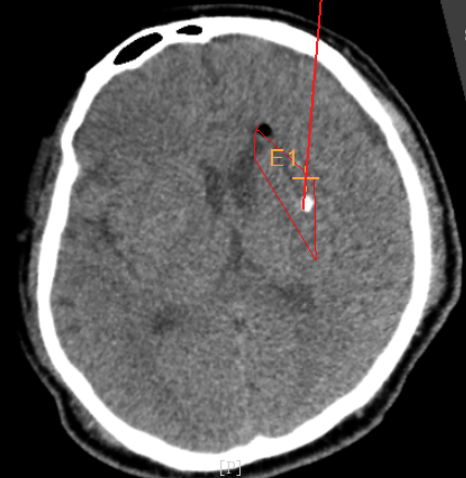

3個(gè)月前CT:腦出血